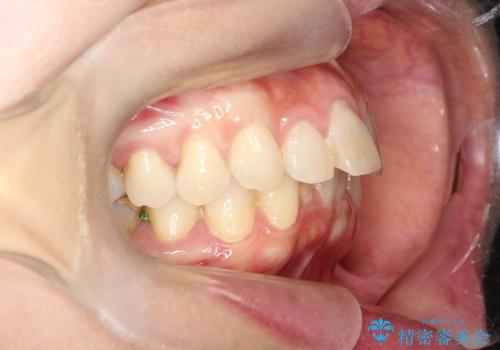

- 前歯の凸凹を主訴に来院されました。

臼歯部の遠心移動を行いながらスペースを作り、インビザラインにて前歯をきれいに並べることができました。

今回の治療計画では臼歯部の遠心移動とIPRを行っています。